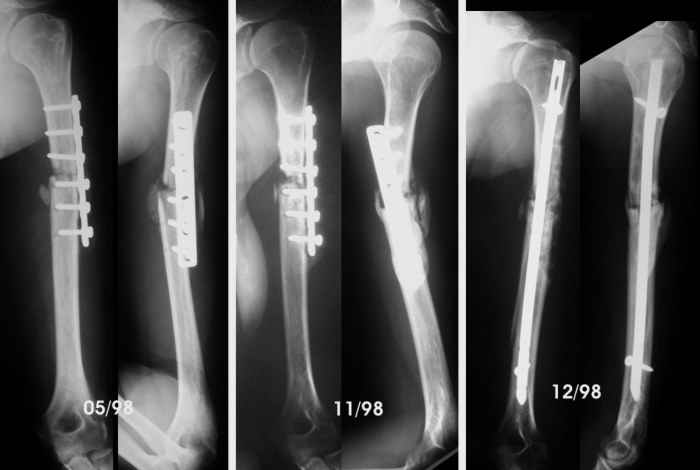

She was close to a tractor power take-off and her clothes caught her. She was pulled towards the tractor and suffered several rib fractures and this humeral fracture (AO-OTA 12-B2). No radial paralysis. She was fixed with Hackettal elastic nailing.

Six months later there was no signs of healing so she accepted to revise the fracture. We used compression plating and autologous iliac bone grafting on April 98.

By the end of May, she complained of sudden pain during physiotherapy, and came with the bottom left x-Ray. We advised to revise the operation, but she wanted to wait in a brace, but by November the humerus hadn't healed so we advised to remove the plate, add more bone graft and nail it. Which we did.